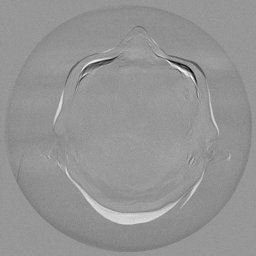

To assess the uncertainty of our method, we performed multiple reconstructions using different random seeds. As shown in Fig. 3, the ground truth and representative sampled images are presented in Fig. 3(a) and (b–d), respectively. The mean reconstruction and pixel-wise standard deviation across runs are displayed in Fig. 3(e) and (f). Only minimal differences are observed between reconstructions, indicating that I2SB produces highly consistent results. These findings confirm that, compared with classical diffusion models, I2SB substantially reduces uncertainty across repeated reconstructions.